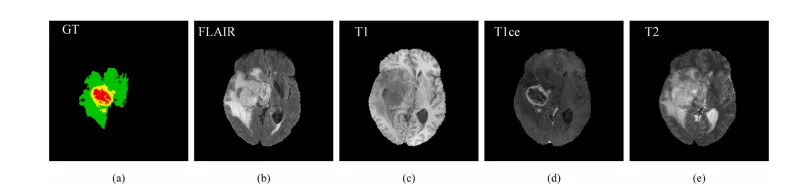

医学图像分割是医学图像处理领域的重要课题。其中,脑肿瘤分割旨在从图像中定位多种类型的肿瘤区域,对临床实践具有重要意义。由于磁共振成像(MRI)在提供软组织高分辨率解剖结构方面的良好能力,它在诊断和治疗脑肿瘤疾病中被广泛应用。为了获得准确分割所需的全面信息,通常需要在脑肿瘤分割中使用具有不同成像参数的多模态MRI扫描。常用的模态包括液体衰减反转恢复(FLAIR)、T1加权(T1)、对比增强T1加权(T1ce)和T2加权(T2)。不同模态的图像捕获了不同的病理信息,并且它们可以有效地相互补充,这在分割多种类型的脑肿瘤区域(如水肿(ED)、坏死和非增强肿瘤(NCR/NET)以及增强肿瘤(ET))中起着至关重要的作用。图1展示了用于脑肿瘤分割的多模态MRI的示例。为简单起见,只选择了整个扫描的一个切片。图1(a)显示了领域专家提供的地面真相(GT)分割标签。绿色、黄色和红色分别表示ED、ET和NCR/NET区域。从图1(b)到(e)可以看出,不同模态的特征差异显著。例如,FLAIR模态可以很好地捕获具有明显边缘或边界的ED区域,而T1ce模态在检测具有高对比度的肿瘤核心(即ET和NRC/NET的联合)方面更为有效。

Fig. 1. An example of multimodal MRI for brain tumor segmentation. (a) The ground truth (GT) segmentation label provided by domain experts (the green, yellow and redrepresent edema (ED), enhancing tumor (ET), and necrosis and non-enhancing tumor (NCR/NET), respectively). (b) The FLAIR modality. © The T1 modality. (d) The T1cemodality. (e) The T2 modality. (For interpretation of the references to color in this figure legend,

图1. 用于脑肿瘤分割的多模态MRI示例。(a)领域专家提供的地面真实(GT)分割标签(绿色、黄色和红色分别表示水肿(ED)、增强肿瘤(ET)和坏死和非增强肿瘤(NCR/NET))。(b)FLAIR模态。(c)T1模态。(d)T1ce模态。(e)T2模态。